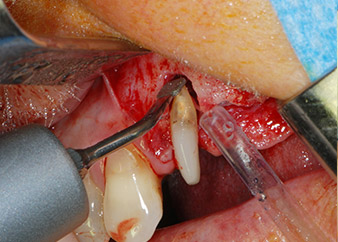

One month later, on the day of surgery, pain and inflammation at tooth 24 were minimal, but mobility of Miller class 2 was still present. After opening the flaps and cleaning the periapical and peri radicular infected tissue, the extent of the bone defect became obvious (Figs. 2 and 3).

At the buccal root, all vestibular and distal bone was missing. Attachment was essentially restricted to the palatal root, underlining the preliminary poor prognosis. Tooth 27 also showed a reduced horizontal attachment and a minimal apical rarefaction (cf. Fig. 1) without clinical symptoms.

total loss of bone and attachment

Fig. 2 and 3: After raising flaps, one month after endodontic revision and initiation of full-mouth periodontal therapy, the buccal root of tooth 24 showed a total loss of bone and attachment.

However, we maintained our initial plan to retain both teeth as temporary bridge abutments during the six-months osseointegration period of the implants. At reentry, the situation would have to be reassessed. First, in an attempt to manage the endo-perio problem, the remaining root surface was carefully debrided with piezoelectric equipment (Piezomed, W&H, used with the spatula-shaped insert S1, originally designed for erosion of the lateral sinus wall) (Fig. 4).

Then the apex was abraded with the same instrument to remove residual infected apical tissue and to reduce possible accessory root-canal ramifications (apicoectomy) (Fig. 5). A retrograde filling was not necessary because the orthograde filling had just been revised.